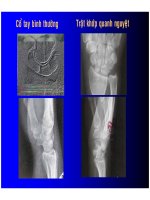

X quang cổ tay thường qui : chủ yếu để chẩn đoán

- Chẩn đoán : Không quá phức tạp ( LS + XQ )

- Thực tế : dễ bỏ sót (khách quan và chủ quan)